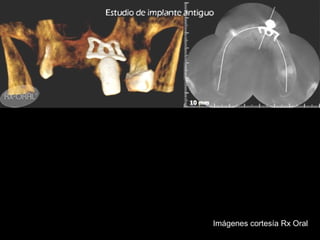

Tomografía Convencional

Imágenes cortesía Rx Oral

Tomografía computarizada

De seno maxilar corte sagital.

Area de implantación

Dentaria.